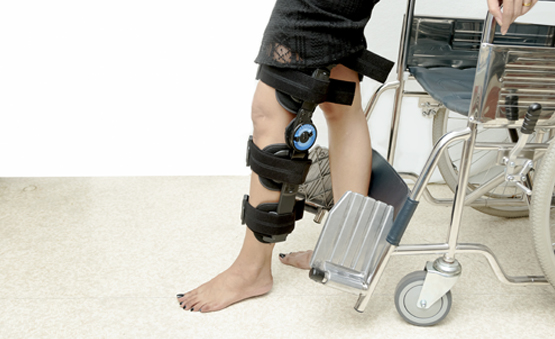

• Debe realizar la rehabilitación que su médico tratante le indique en el momento adecuado.

• Usar el movilizador pasivo continuo de acuerdo a recomendaciones de su médico

Para lograr una recuperación completa y aprovechar al máximo el beneficio de esta cirugía es recomendable que los pacientes reciban un programa de rehabilitación institucional después de la intervención quirúrgica que ayudará a mejorar la inflamación y a recuperar la funcionalidad de la rodilla. Esta fisioterapia incluso permitirá recuperar el patrón de marcha normal y ayudará a otras articulaciones afectadas a mejorar su funcionamiento.